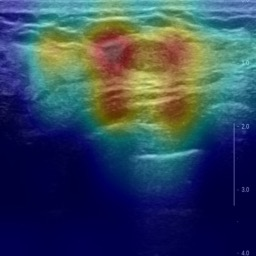

Ultrasonography is an important routine examination for breast cancer diagnosis, due to its non-invasive, radiation-free and low-cost properties. However, it is still not the first-line screening test for breast cancer due to its inherent limitations. It would be a tremendous success if we can precisely diagnose breast cancer by breast ultrasound images (BUS). Many learning-based computer-aided diagnostic methods have been proposed to achieve breast cancer diagnosis/lesion classification. However, most of them require a pre-define ROI and then classify the lesion inside the ROI. Conventional classification backbones, such as VGG16 and ResNet50, can achieve promising classification results with no ROI requirement. But these models lack interpretability, thus restricting their use in clinical practice. In this study, we propose a novel ROI-free model for breast cancer diagnosis in ultrasound images with interpretable feature representations. We leverage the anatomical prior knowledge that malignant and benign tumors have different spatial relationships between different tissue layers, and propose a HoVer-Transformer to formulate this prior knowledge. The proposed HoVer-Trans block extracts the inter- and intra-layer spatial information horizontally and vertically. We conduct and release an open dataset GDPH&GYFYY for breast cancer diagnosis in BUS. The proposed model is evaluated in three datasets by comparing with four CNN-based models and two vision transformer models via a five-fold cross validation. It achieves state-of-the-art classification performance with the best model interpretability.